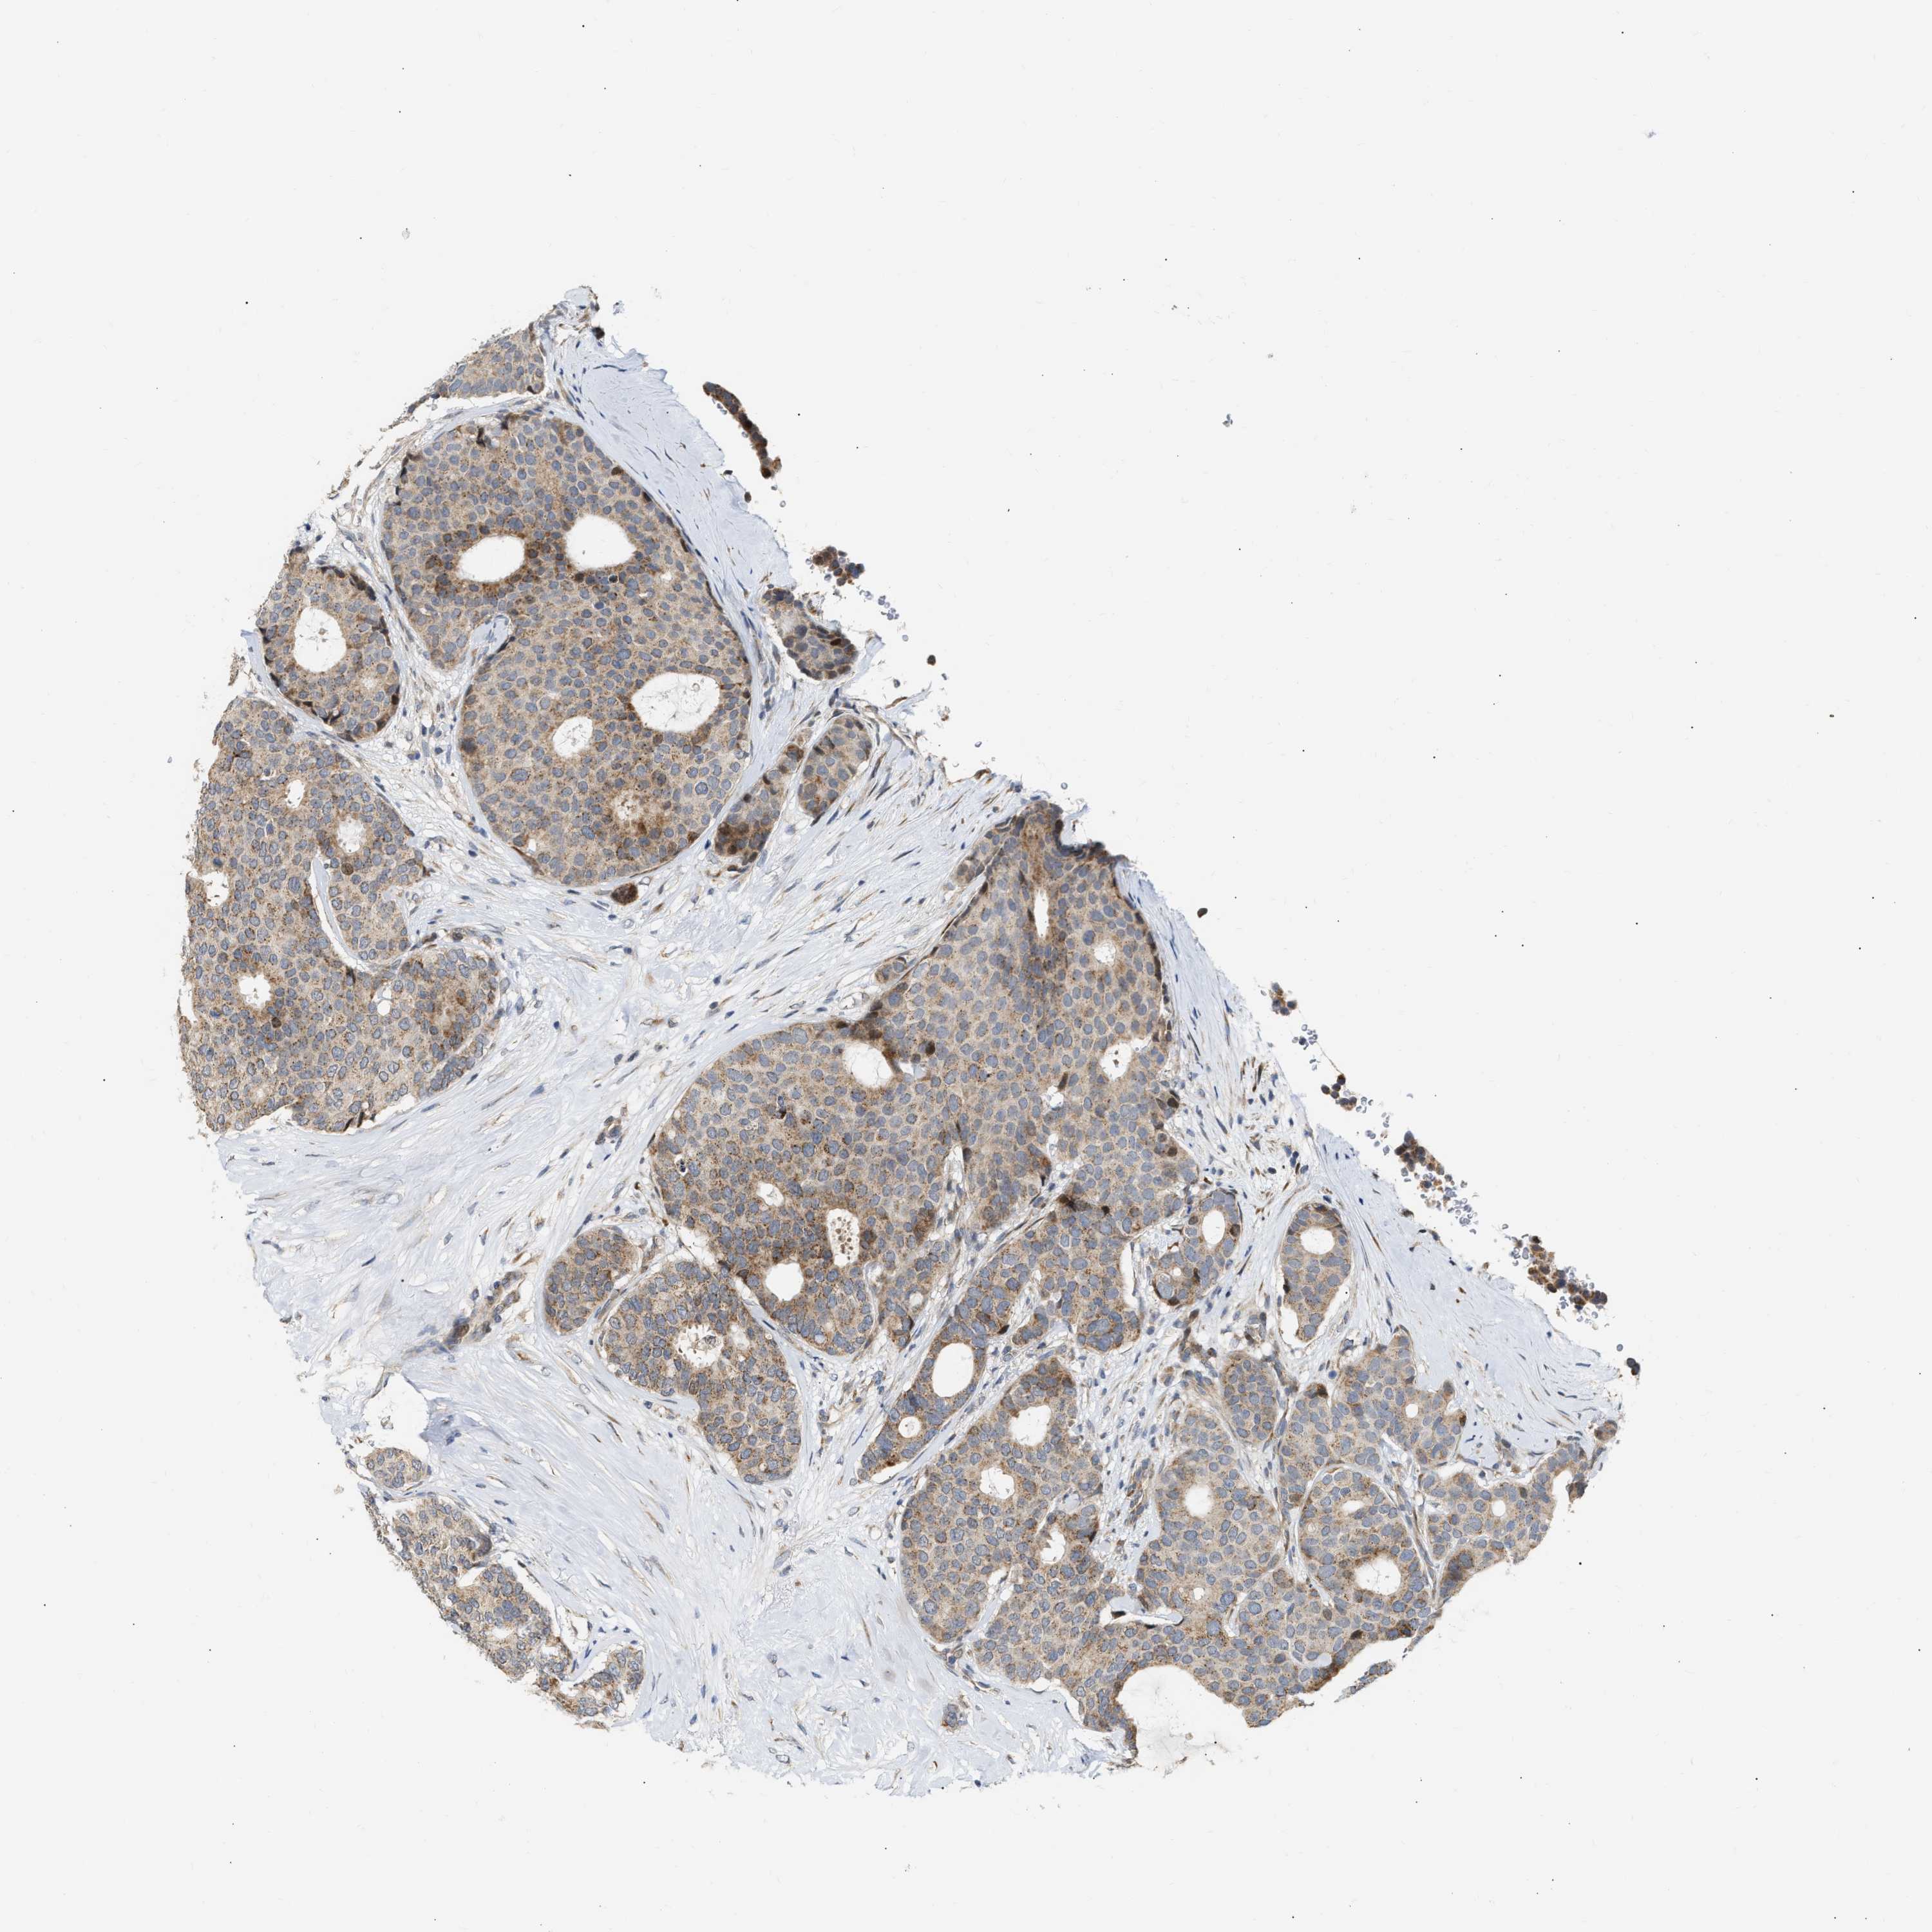

CANCER BREAST CANCER Show tissue menu

BRCA TCGA BRCA VALIDATION PROTEIN EXPRESSION